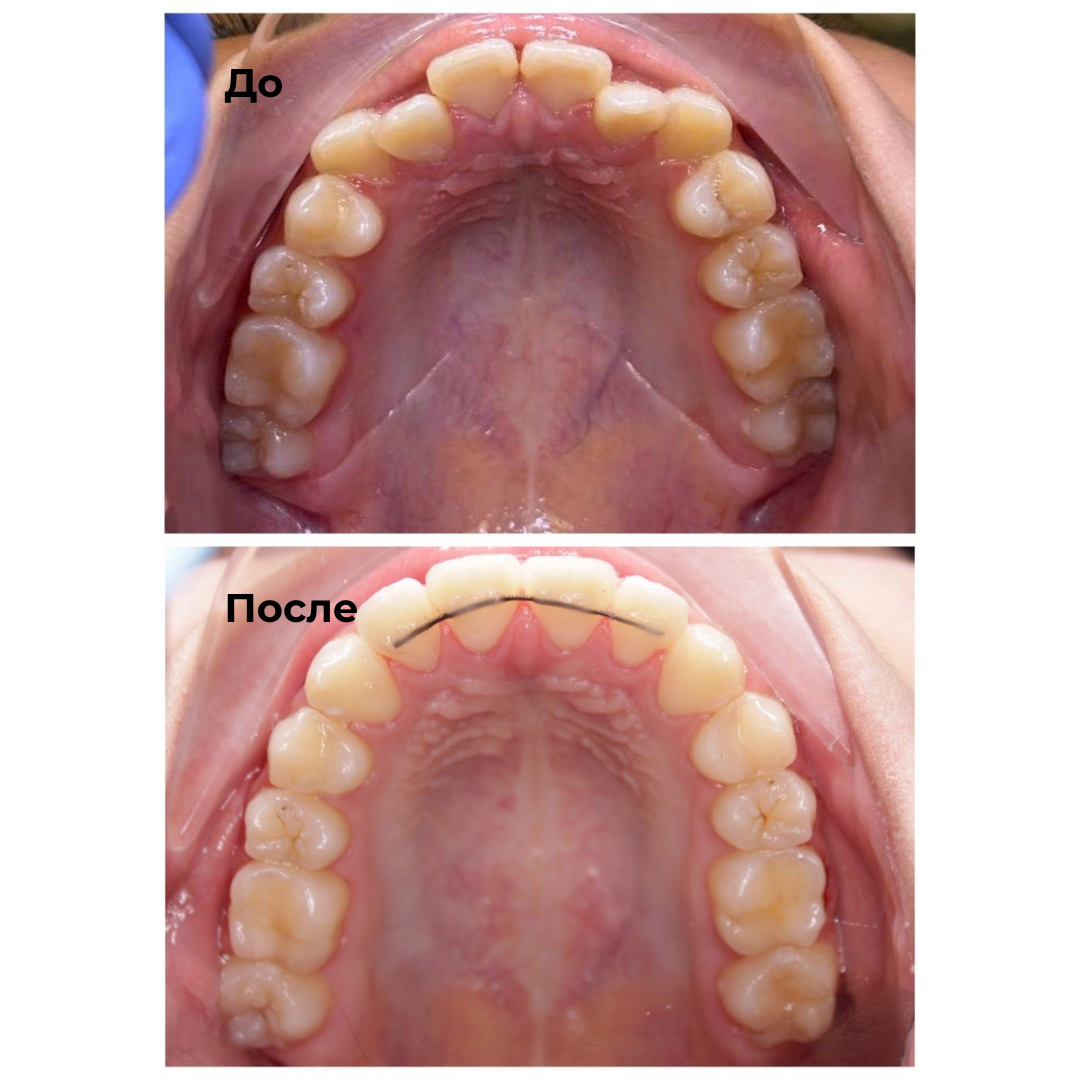

Такие результаты получают наши пациенты после лечения

Каждый случай - индивидуальный, но результат один: ровные зубы

Запишитесь на консультацию — подберём оптимальный план лечения под ваш случай.

Исправляет прикус и выравнивает зубы у детей, подростков и взрослых.

✔ Работает со сложными случаями скученности и узкой челюсти у детей